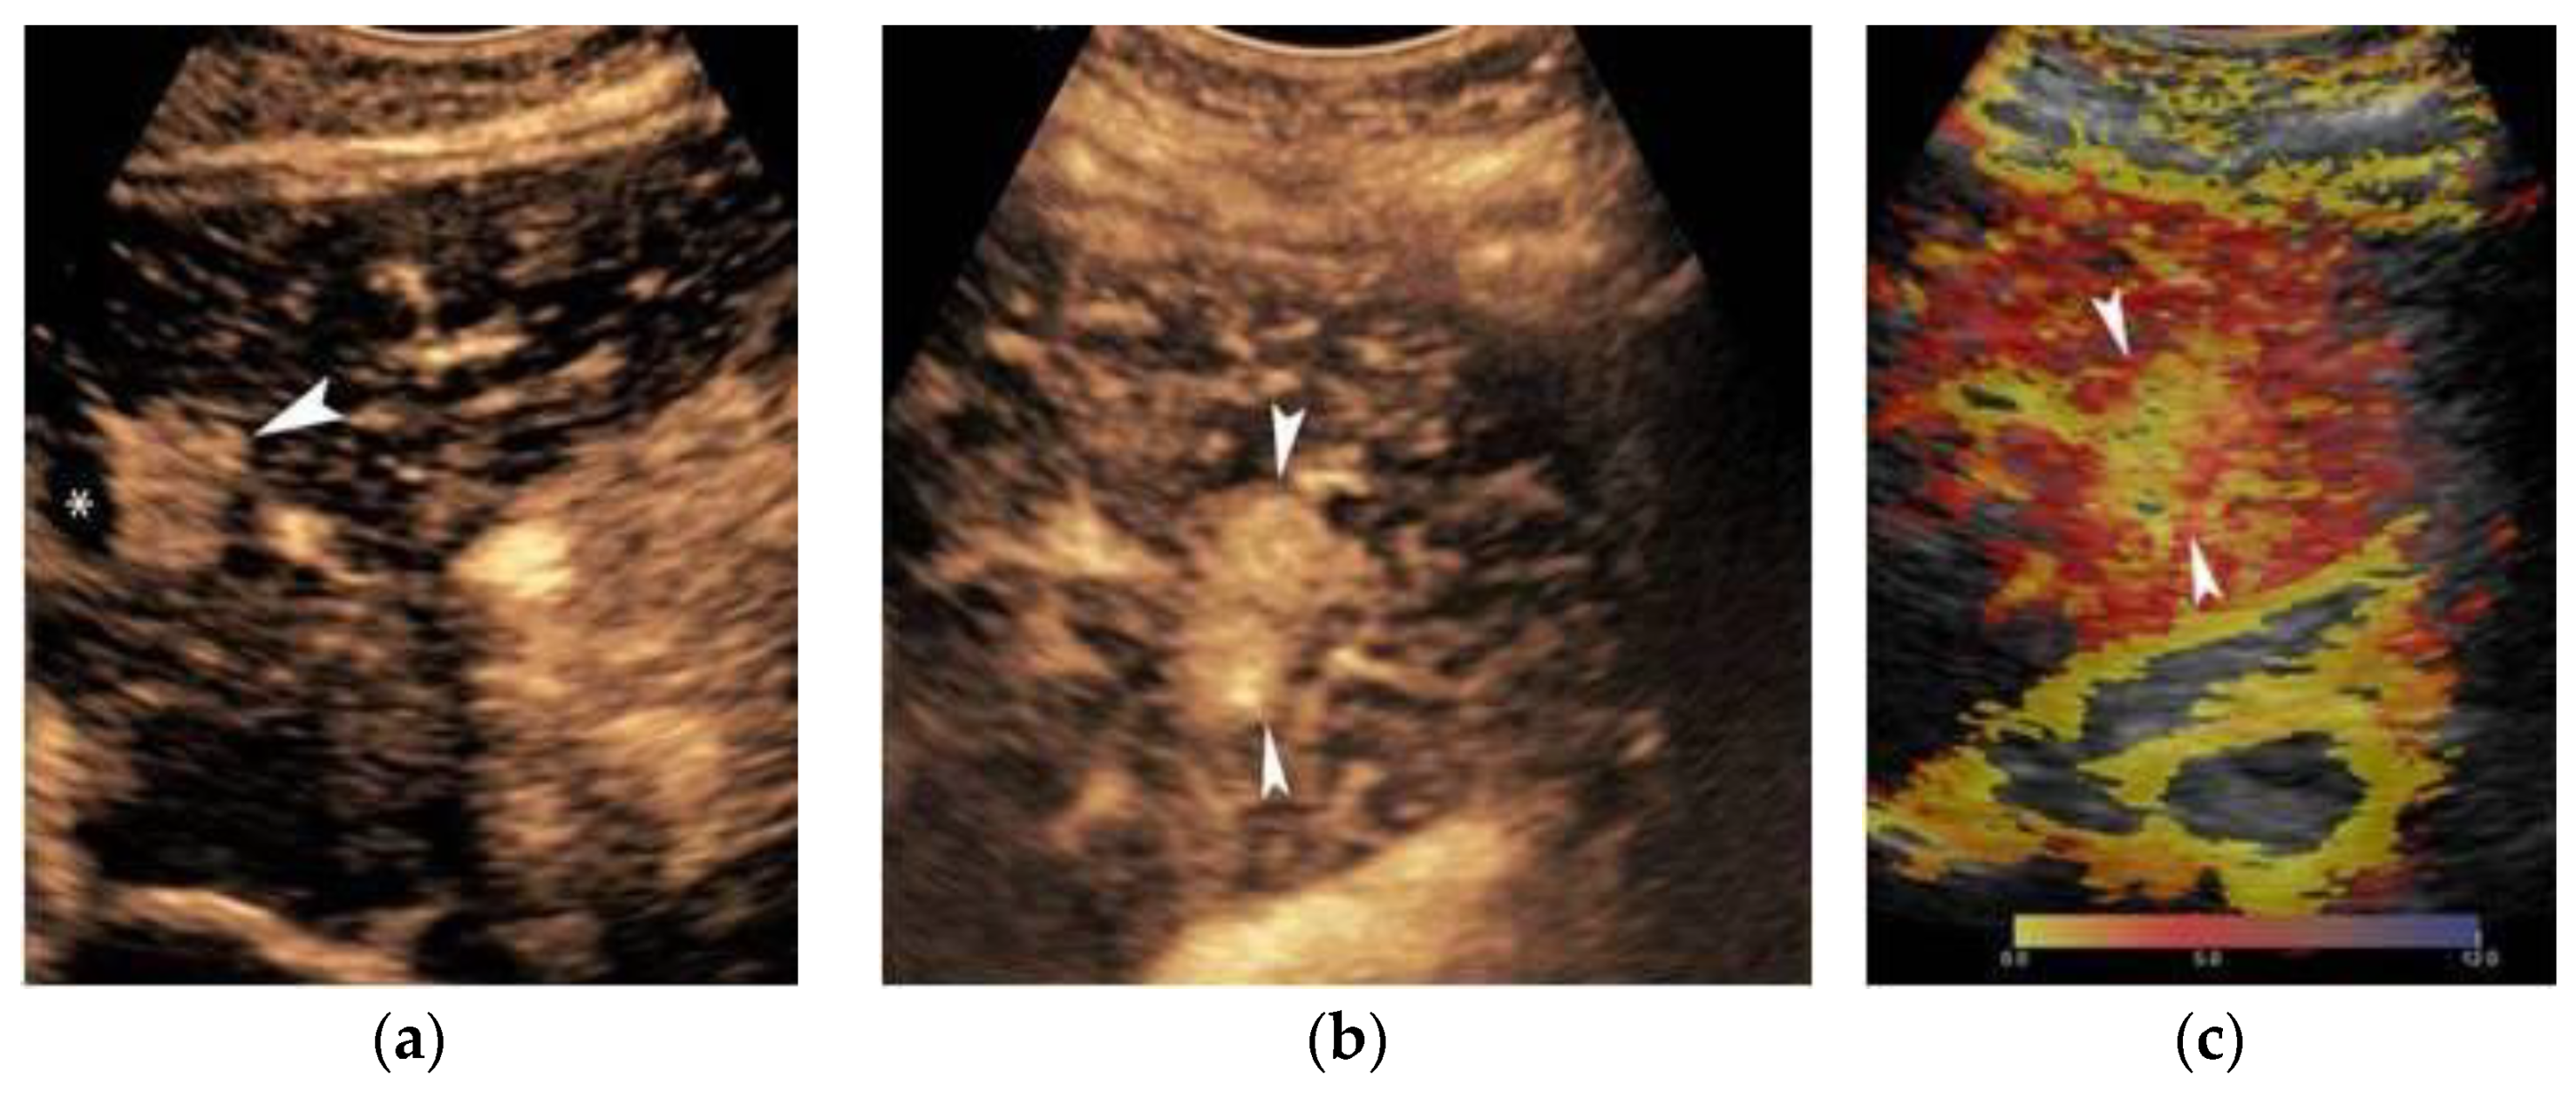

2. Ultrasound

3. Contrast-Enhanced Ultrasound